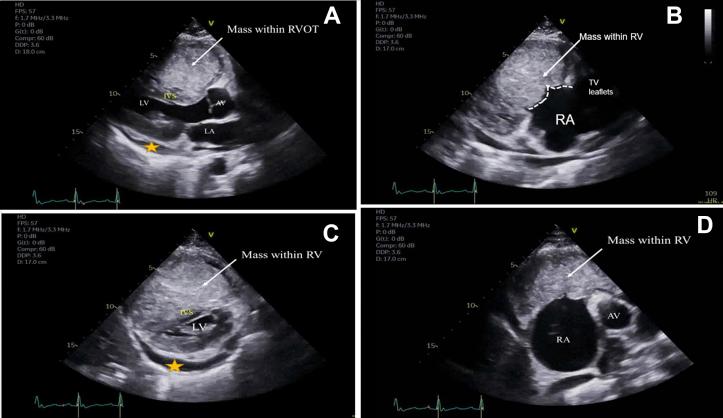

超声心动图在诊断一名表现为右心衰竭的年轻患者转移性睾丸癌中的作用

Role of Echocardiography in Diagnosing Metastatic Testicular Carcinoma in a Young Patient Presenting as Right Heart Failure.

• Metastatic GCTs may initially present as right heart failure. • TTE and TEE can diagnose cardiac metastasis and monitor cardiac function. • Multimodality imaging informs about tumor burden in metastatic cardiac tumors.

摘要

• 转移性生殖细胞肿瘤(GCTs)最初可能表现为右心衰竭。

• 经胸超声心动图(TTE)和经食管超声心动图(TEE)可诊断心脏转移并监测心脏功能。

• 多模态成像可提供有关转移性心脏肿瘤中肿瘤负荷的信息。